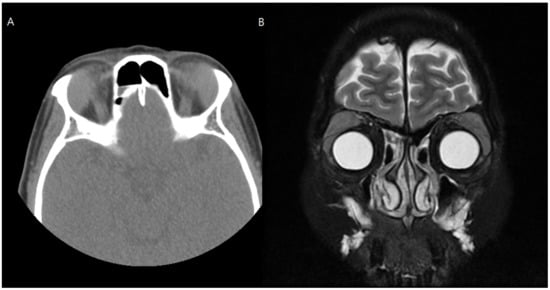

A 52-year-old female patient with a chief complaint of swelling in both upper eyelids accompanied by diplopia visited our medical center. In orbital CT and magnetic resonance imaging scans, bilateral lacrimal gland hypertrophy was observed (Figure 3). Incisional biopsy of the bilateral lacrimal gland was performed to differentiate a diagnosis of lacrimal gland lymphoma from that of immunoglobulin G4 (IgG4)-related ophthalmic disease. The lacrimal gland tumor was approached via transconjunctival incision, and a biopsy was performed. Lacrimal gland biopsy with immunohistochemical staining of IgG4 showed a number of benign cells. Her blood test results showed increased IgG4 levels, and IgG4-related lacrimal adenitis was confirmed.

Figure 3. Preoperative computed tomography (A) and magnetic resonance imaging (B) of Case 2. Enlarged lacrimal glands were noted in both orbits.